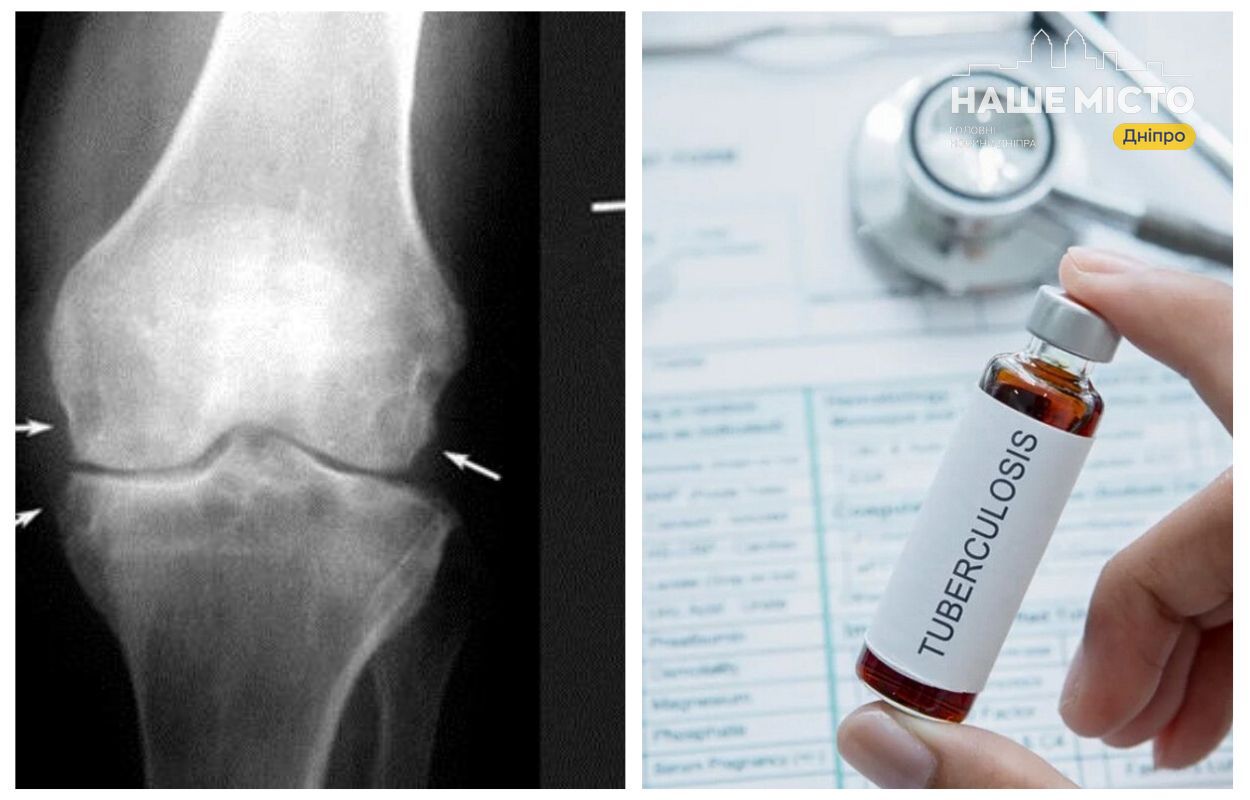

У Дніпропетровському обласному медичному центрі соціально значущих хвороб відзначають, що позалегеневий туберкульоз може вражати різні органи, крім тих, що майже не контактують із кровообігом, наприклад, волосся та нігті, і часто маскується під інші захворювання.

Як пояснює Наталія Бутковська, завідувачка фтизіопульмонологічного консультативно-діагностичного відділення, симптоми позалегеневого туберкульозу часто є неспецифічними, через що пацієнти тривалий час лікуються у різних спеціалістів, не отримуючи правильного діагнозу.

- Тривалі або нестандартні запалення, які не піддаються звичайному лікуванню;

- Офтальмологічні проблеми, що зберігаються понад місяць;

- Безпліддя у жінок;

- Підозра на ураження кісток або центральної нервової системи.

Для точного діагнозу у центрі проводять спеціальні дослідження, зокрема аналізи сечі, мазки для дослідження методом GeneXpert, а також обстеження рідин організму на наявність туберкульозної палички.

Тривалість лікування залежить від локалізації захворювання:

- Туберкульоз кісток – до 9 місяців;

- Ураження центральної нервової системи – близько 10 місяців.

За рік у центрі спостерігали по 2-3 випадки менінгіального туберкульозу, який частіше зустрічається у пацієнтів з імунодефіцитом.

Самовиліковування та ризики

У людей із міцним імунітетом приблизно 25% випадків позалегеневого туберкульозу можуть закінчитися самовиліковуванням. Разом з тим, ризик розвитку захворювання зростає при наявності супутніх хронічних хвороб.

Для жителів Дніпропетровщини важливо звертатися до фтизіопульмонологів при тривалих проблемах зі здоров’ям, які не піддаються звичайному лікуванню, адже вчасна діагностика і лікування позалегеневого туберкульозу підвищують шанси на повне одужання.